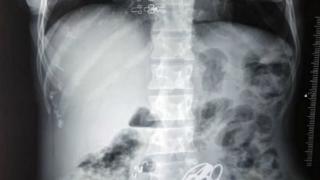

Лекари откриха в храносмилателния тракт на индийка килограм и половина различни предмети, включител...